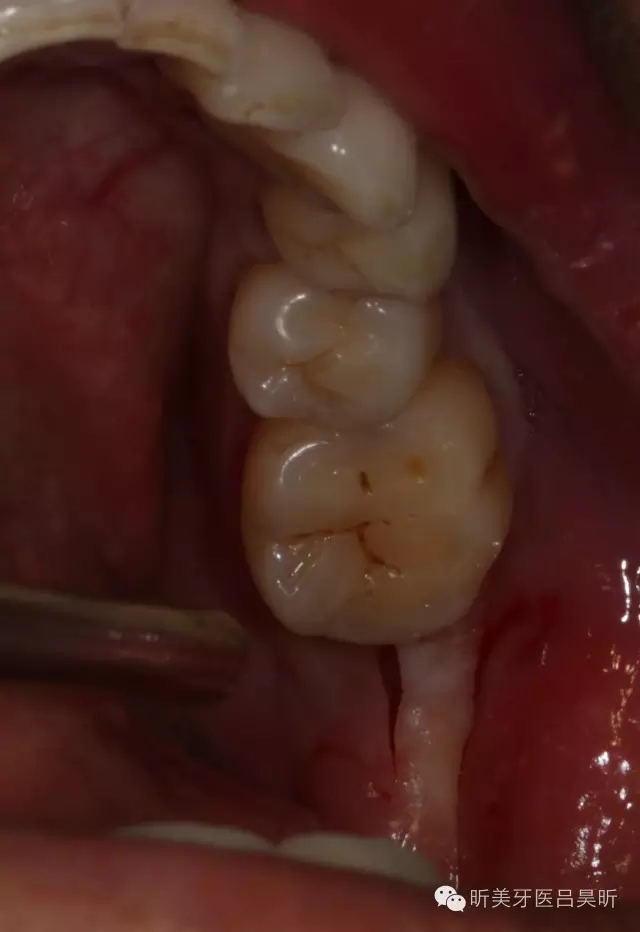

患者,男性,47缺失兩年。

術(shù)前口內(nèi)檢查,可見(jiàn)牙槽骨寬度良好,角化齦量適中